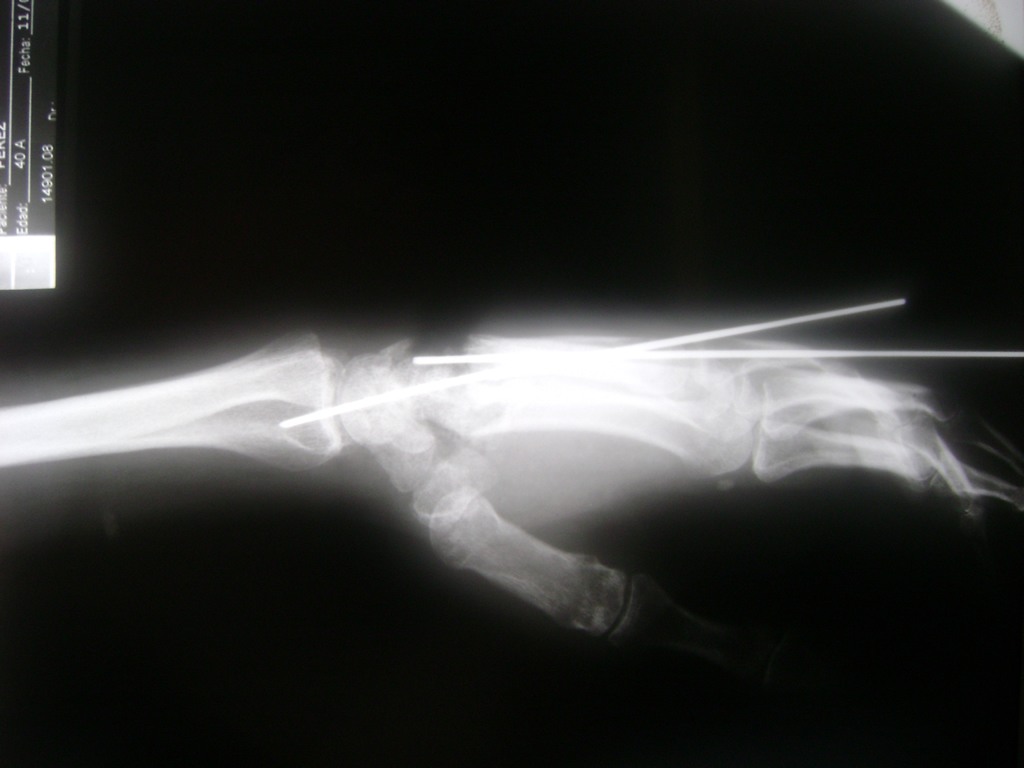

Clavícula

Los procedimientos más comunes en cirugía de la mano son aquellos destinados a reparar traumatismos, incluyendo lesiones de tendones, nervios, vasos sanguíneos, y articulaciones; huesos fracturados; y quemaduras, cortes, y otros daños de la piel.